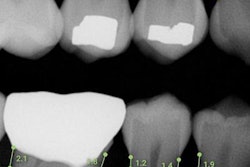

A CBCT scan and segmentation from one patient. The false negatives and false positives for the teeth and jaw are colored in the difference map. Image courtesy of Wang et al (2021), "Multiclass CBCT Image Segmentation for Orthodontics with Deep Learning," J Dent Res.In one example, the difference map showed the algorithm erred mostly at the edges of segmentation with a difference of about 1 pixel. The algorithm also missed some thin bony structures around the maxillary sinus, the authors noted.